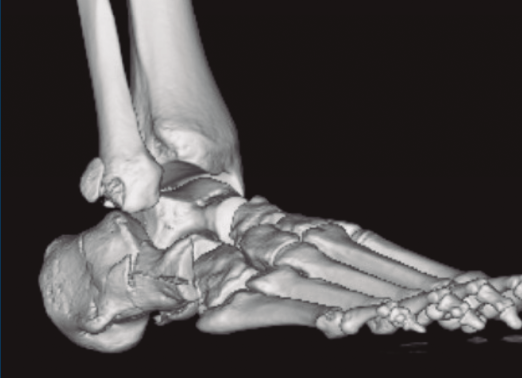

Figura 1. Luxación del astrágalo en mortaja tibioperonea, fractura maléolo peroneo y espacio subperoneo ocupado por calcáneo.

Se trata de un varón de 19 años que ingresa en reanimación tras precipitarse desde una altura de aproximadamente 10 metros. El paciente presenta una fractura estallido de L3 con afectación del canal medular junto con una fractura del vértice inferior de L4, así como una fractura luxación de calcáneo, asociada a una fractura del maléolo peroneo y del maléolo tibial posterior (Figuras 1 a 6) diagnosticadas mediante TC total body (por eso no se dispone de radiografías simples al momento del ingreso). Como podemos comprobar, se trata de una fractura de doble trazo de tipo hundimiento/depresión de la carilla articular (Figuras 5 y 6).

Figura 4. Luxación fragmento posterolateral.